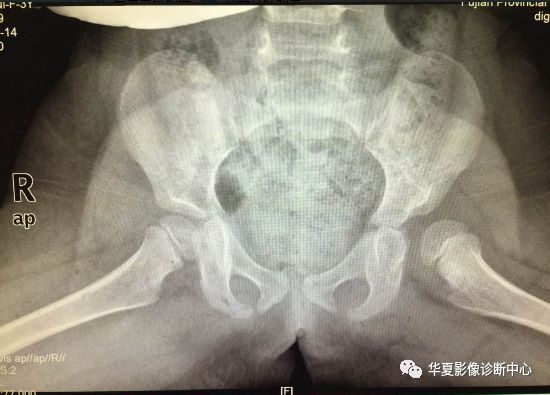

上图:骨盆蛙式位

4.髋臼指数

从髋臼外缘向髋臼中心连线与H线相交形成的锐角,称为髋臼指数。

出生时,髋臼指数为25.8°~29.4°,6个月婴儿19.4°~23.4°,2岁以上者在20°内。

当小儿步行后此角逐年减小,直到12岁时基本恒定于15度左右。大于正常值者说明臼顶倾斜度增加,为髋臼发育不良。多数学者认为超过30°就有明显脱位趋向。

6. Shenton线:

正常闭孔上缘弧形线与股骨颈内侧弧形线相连在一个抛物线上,称为Shenton线,髋脱位、半脱位病例,此线完整性消失。

7.外侧线(Calve线)

外侧线(Calve线)即髂翼的外侧面与股骨颈外侧面的弧形连线,正常为连续的。